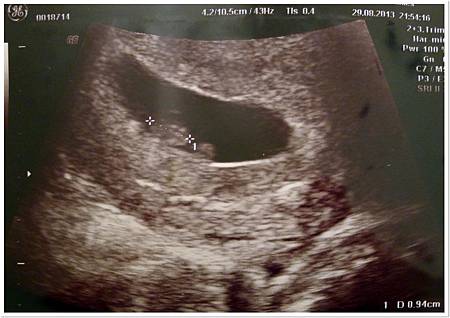

看著他從一團黑嬤嬤的東西長成有頭有手有腳真的滿奇妙的@@